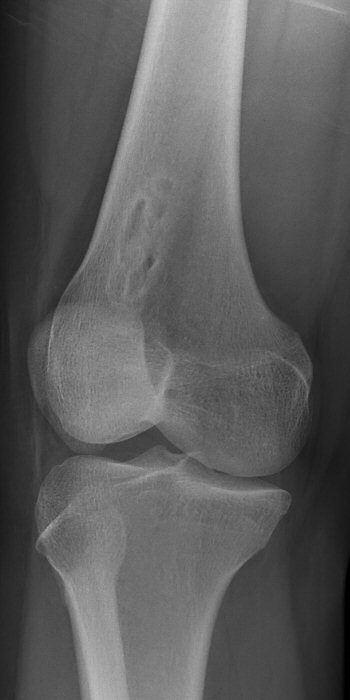

- Non-ossifying fibroma = NOF: felaktig ossifikation, oftast hos pojkar 5-15 år i metafys av långa rörben, lytiskt, "bubbligt" utseende med sklerotiska kanter. Kan ge fraktur som i så fall behandlas på vanligt sätt. Kan någon enstaka gång opereras med curettage och bengraft vid stor påverkan på kortex med frakturrisk. Brukar annars läka spontant, kan följas med röntgenkontroller årligen. [2]

Två exempel på NOF i distala femur